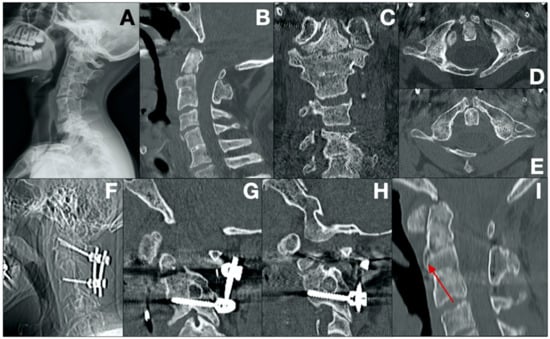

- Case 8 (Figure 4)